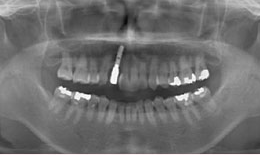

治療後

上顎

保存困難な歯を抜歯後、インプラントを1本埋め込み、セラミックスクラウンを被せた